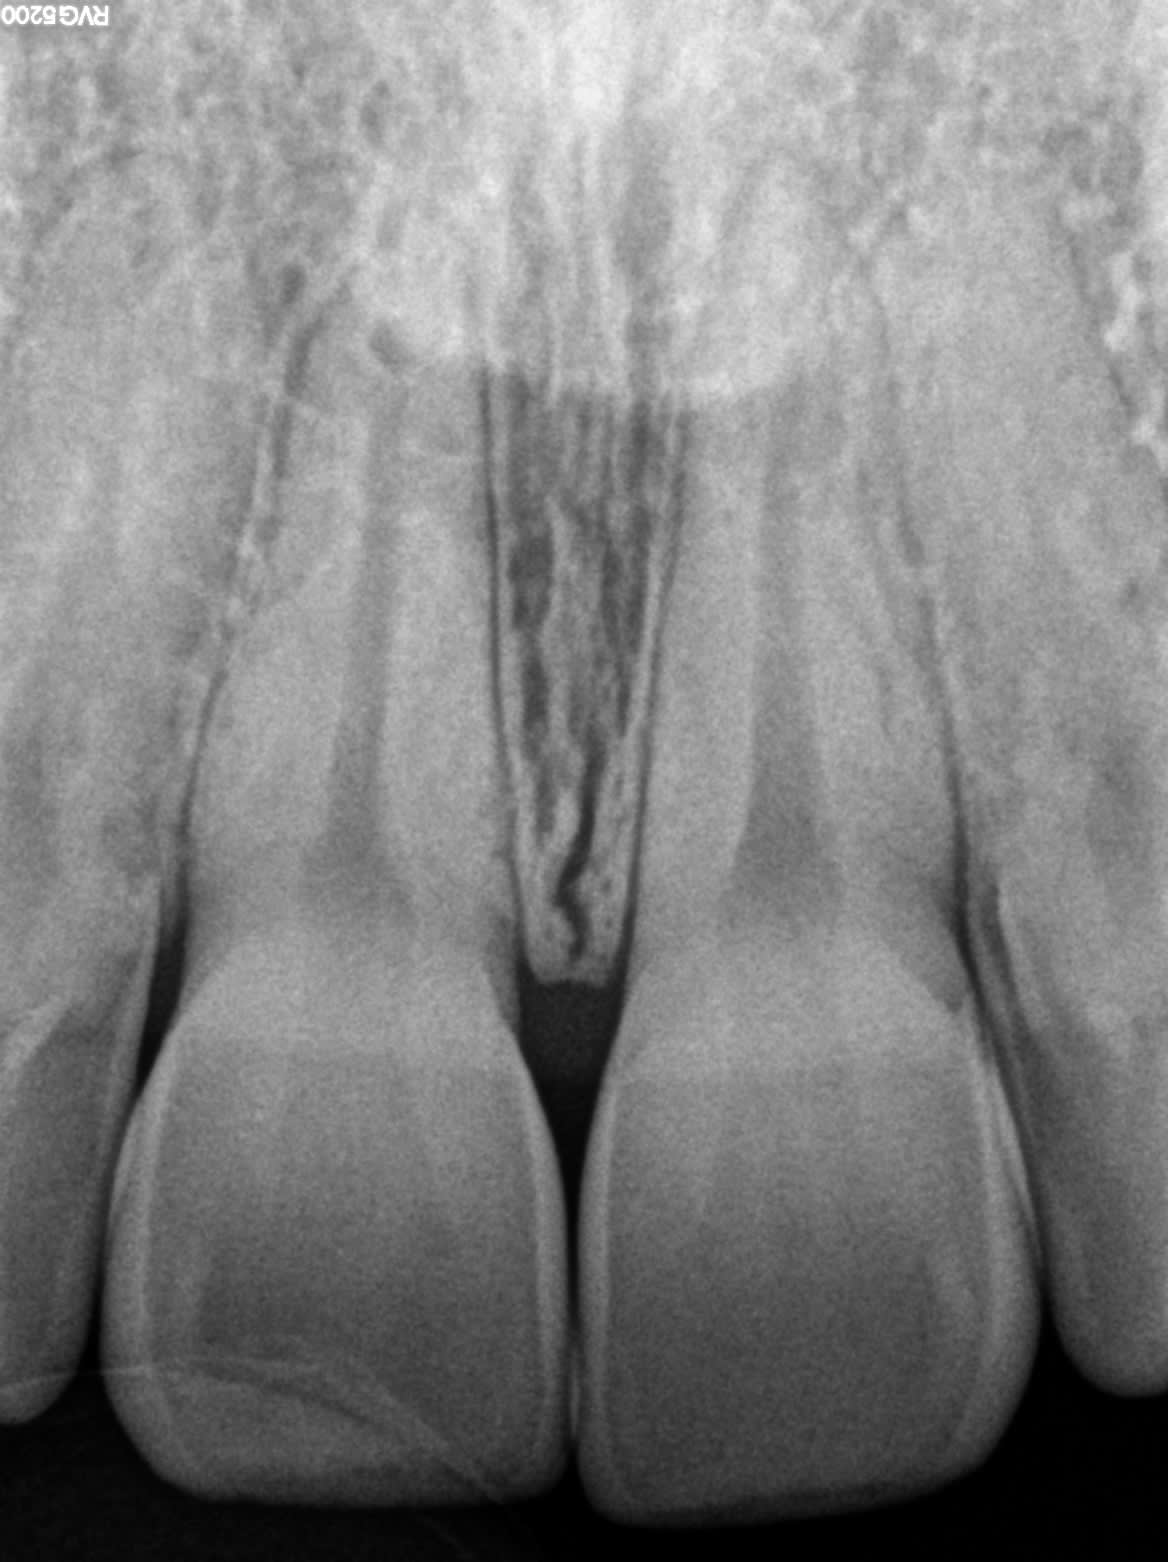

Voilà la rétro :)

J'ai l’impression de voir 2 boulettes de résorption interne dans les 1/3 apicaux sur les centrales ?

> J'ai l’impression de voir 2 boulettes de résorption interne dans les 1/3 apicaux

> sur les centrales ?

Idem, mais en cherchant on voit toujours des trucs louches, faire un CBeam ?!

Il n'y a aucune douleur, aucun symptôme hormis un changement de couleur léger, et aucun signe radiologique net...